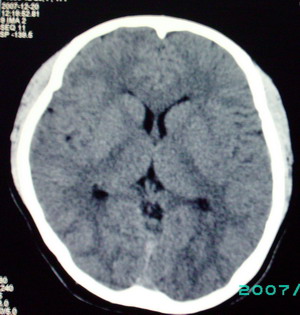

以下是引用九目段在2007-12-24 14:55:00的发言:[br]1,年轻女性[br]2,ct表现:左侧脑室三角区可见一不规则小明显强化的结节,中央见小低密度,侧脑室无扩张。[br]分析:[br]常见的有三种肿瘤好发三角区:[br]1,脉络丛乳头状瘤,好发于年轻者,明显强化,实性,分泌脑脊液,常伴有侧脑室扩大,肿瘤较小可以脑室扩大不明显,不能排除,但小结节尚不易形成坏死腔。[br]2,室管膜瘤,好发于儿童及青少年,明显强化,易坏死,大时伴脑室扩张。[br]3,脑膜瘤,明显强化,圆形,界请,无脑积水,一般不坏死。[br]诊断:[br]左侧脑室三角区结节,考虑室管膜瘤可能性大,不排除脉络丛乳头状瘤和脑膜瘤(因病史较长)。[br][br][本贴已被 九目段 于 2007-12-24 15:13:35 修改过]